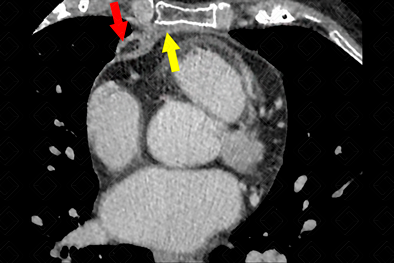

Texto alternativo para a imagem Créditos : Dra. Elazir Mota - Rio de Janeiro/RJ

Descrição das imagens: Tomografia computadorizada do tórax, janela de mediastino. Observa-se lesão ovalada, com densidade de gordura no seu interior (setas vermelhas), associada a espessamento do pericárdio (seta amarela), em paciente com dor torácica aguda, compatível com necrose da gordura epipericárdica.

• Tomografia computadorizada de tórax: Observamos uma imagem arredondada, encapsulada, com densidade de gordura, podendo ou não estar associado a espessamento do pericárdio e, até mesmo, derrame pleural.